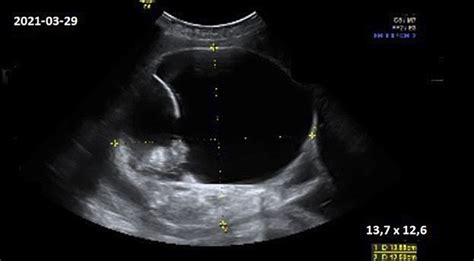

Jei dar nepadarėte - 11-13 savaitę atliekamas pirmasis ultragarsas (t. y. NT tyrimas), kuris padeda įvertinti vaisiaus vystymąsi ir riziką dėl genetinių sindromų. Kraujo tyrimai gali būti atliekami kartu su echoskopija (t. y. pirmasis nėštumo trimestras skriningas). Būtina tęsti folio rūgšties vartojimą ir pasitarti su gydytoju dėl kitų papildų.